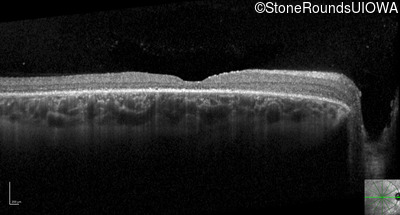

Optical Coherence Tomography - Right - 20/125 +1 sc

Exemplar / OCT Stack

OCT Stack